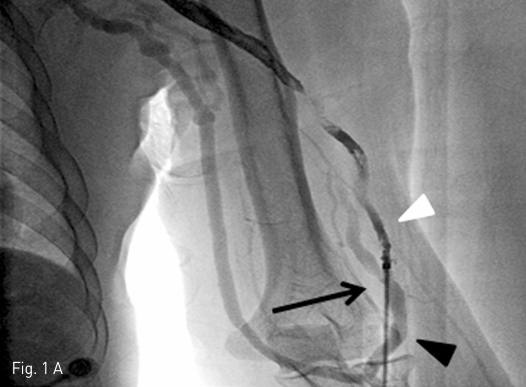

Fig 1A

A. A fistulography via the arterial limb of graft shows a fistula (black arrow) between the arterial limb of the graft (white arrowhead) and an adjacent native cephalic vein of left upper arm (black arrowhead).